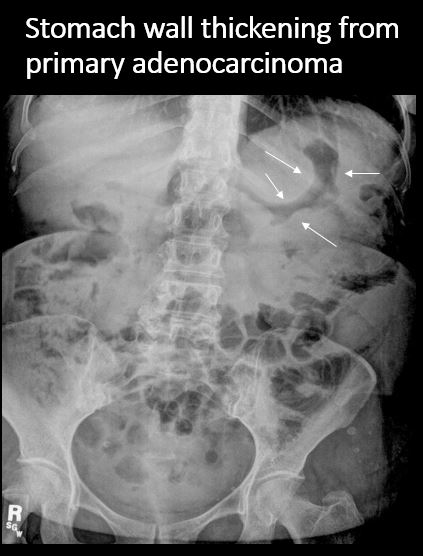

There is thickening of the wall of the stomach. [Yes/No]